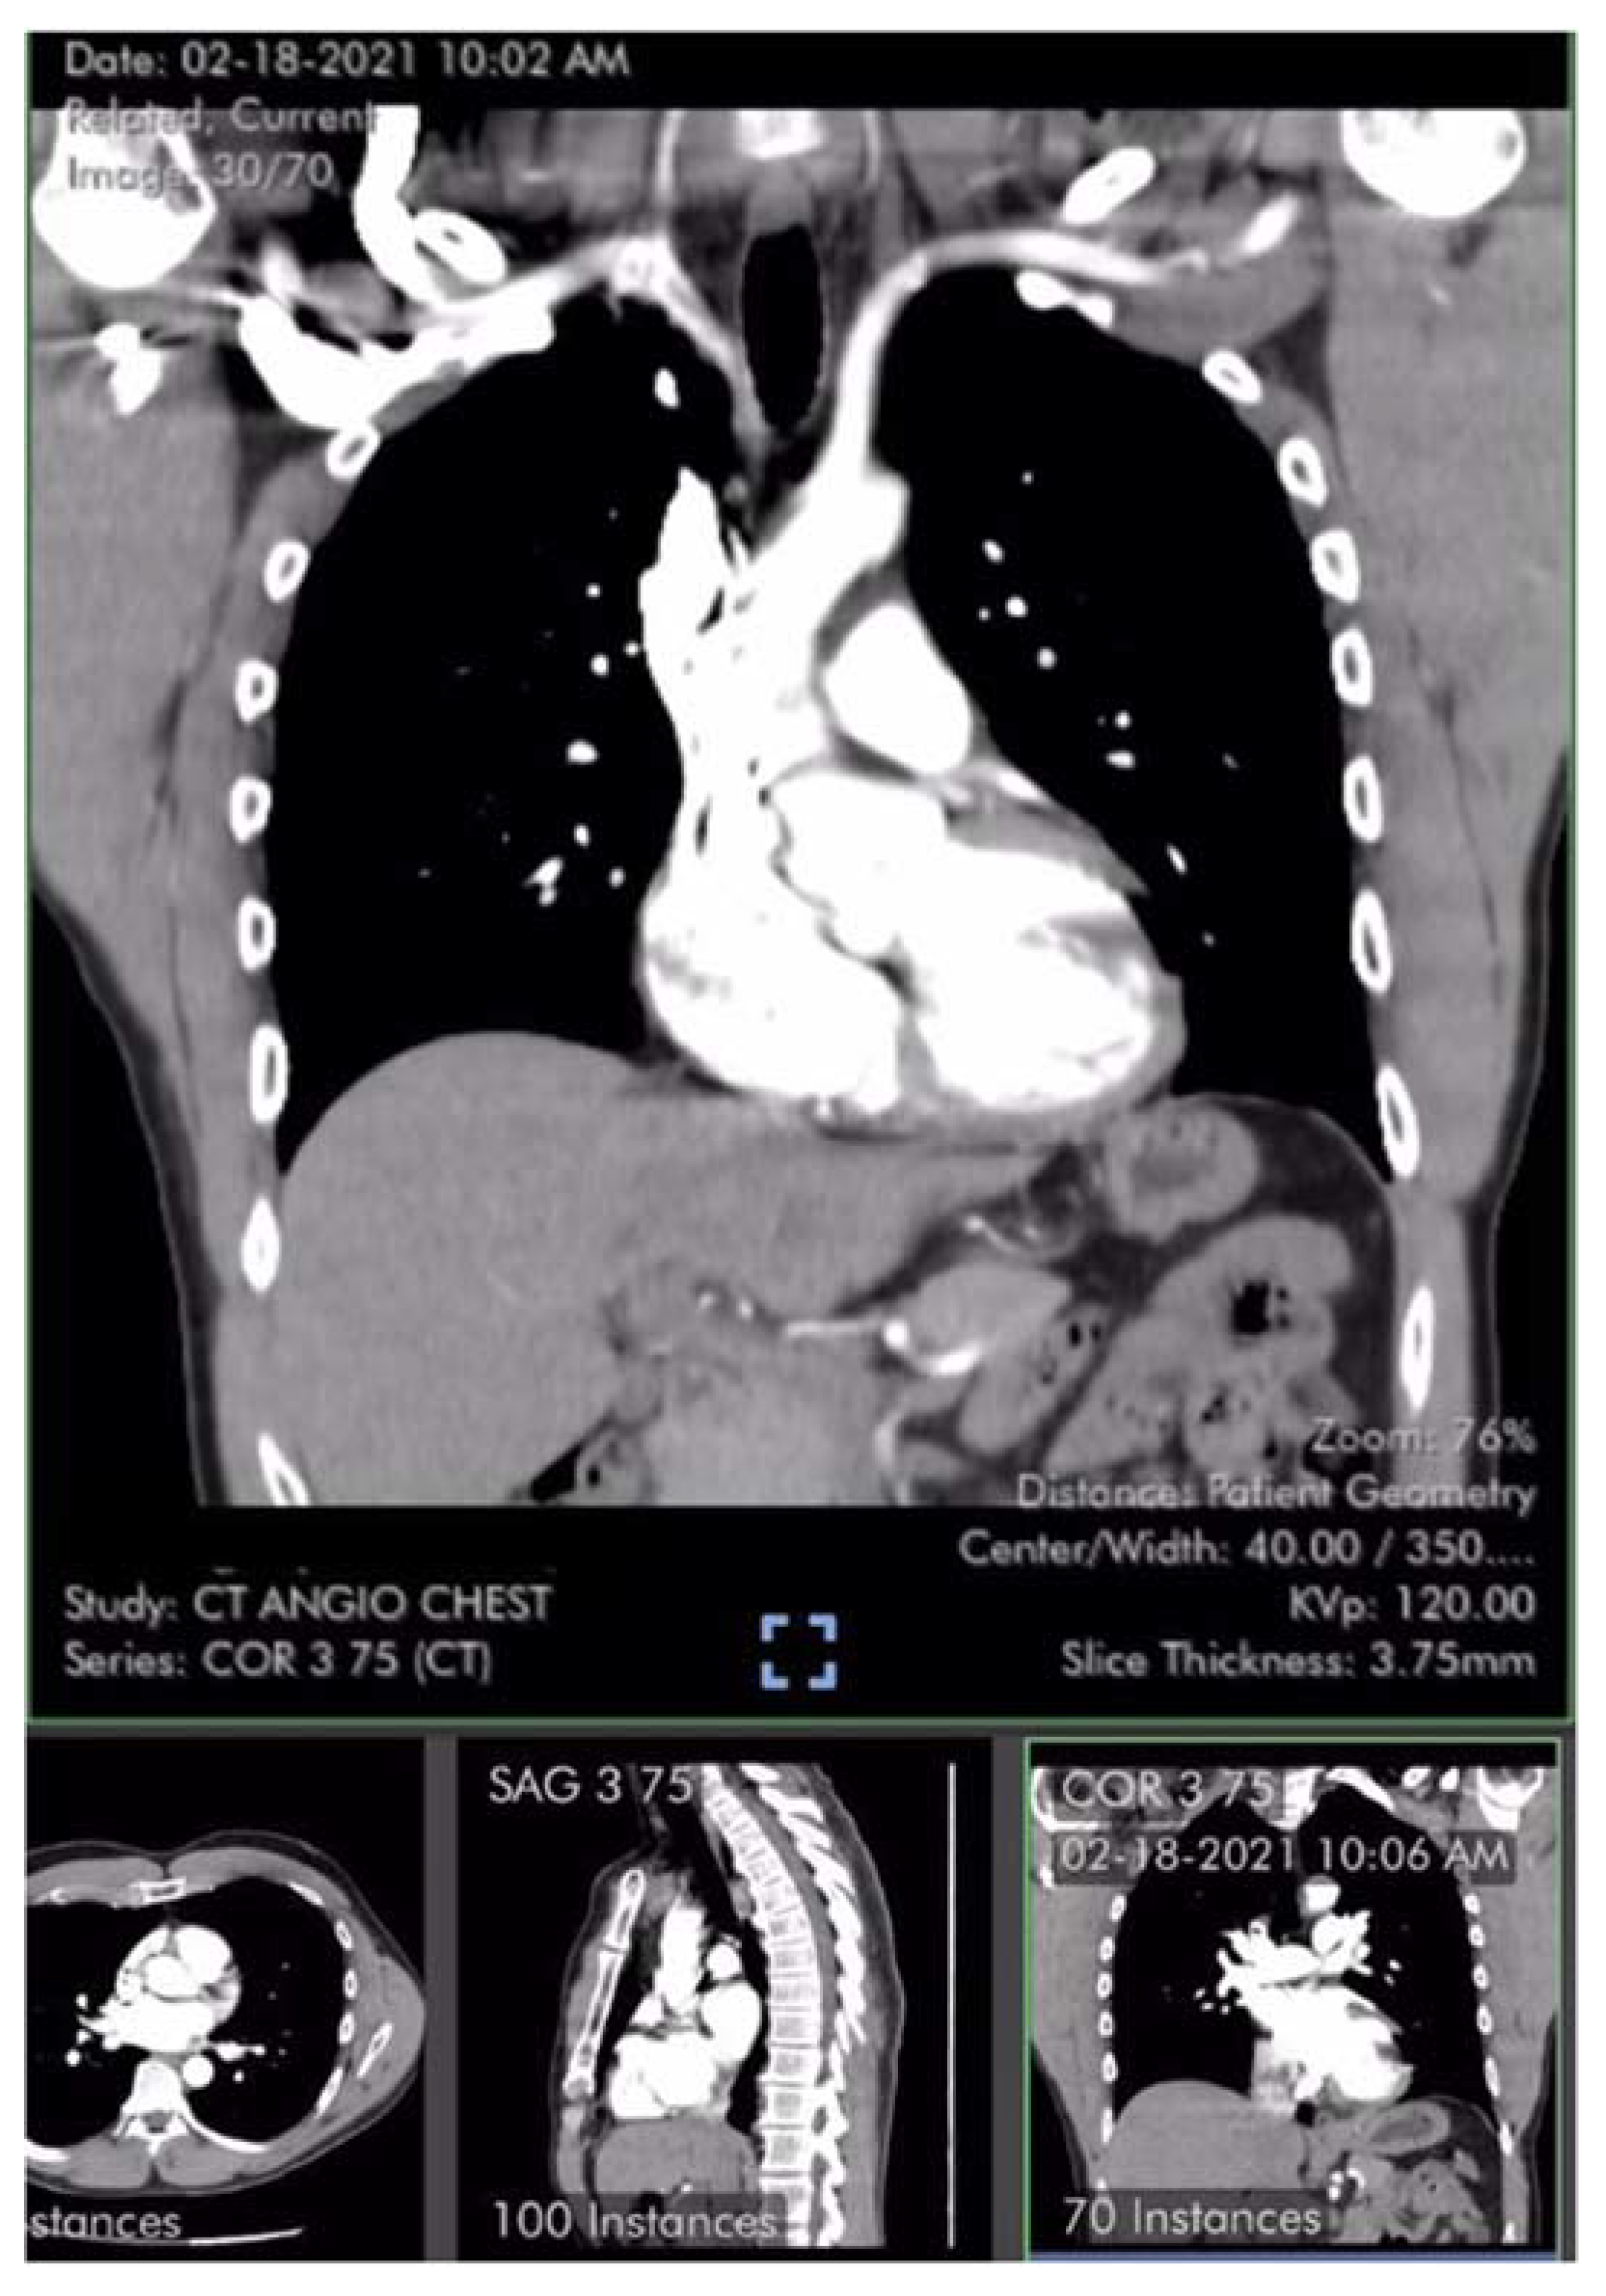

Case #1 is a previously healthy 49-year-old male physician athlete, body mass index (BMI) 23, non-smoker with a history of mild exercise-induced asthma treated with albuterol. Patient completed the primary series of Pfizer mRNA COVID-19 vaccine (BNT162b2) in January 2021. Approximately three weeks after the second dose patient suddenly developed severe fatigue, flu-like symptoms, tachycardia, palpitations, orthostasis, right-sided chest pressure and dyspnea on exertion. COVID PCR testing was negative. Transthoracic echocardiogram revealed normal left ventricular function with an ejection fraction (EF) of 65%, normal right ventricular size and function and a tricuspid regurgitation (TR) jet of 3.09 m/s (Figure 1). Estimated right ventricular systolic pressure (RVSP) of 42 mmHg was interpreted as mild/moderate pulmonary hypertension (Table 1). Laboratory studies including brain natriuretic peptide (BNP) 22 pg/ml (reference range <900 pg/ml) were unremarkable except for elevated low-density lipoprotein (LDL) cholesterol and hematocrit of 50%. Pulmonary computer tomography (CT) angiogram with 3D reconstruction of the PA tree was normal without evidence of pulmonary clots (Figure 2 and Figure 3). Patient subsequently developed 15 lbs of fluid gain and generalized swelling, neck pressure, headaches and a feeling of “being hung upside down” consistent with jugular vein distention (JVD) and cerebral venous congestion. The resting oxygen saturation (SpO2) was 92% and there was new onset systolic and diastolic arterial hypertension. Symptoms and chest pressure occurred at rest and were exacerbated by exertion. Exercise and functional limitations were consistent with New York Heart Association (NYHA) Class 3-4. Serial echocardiograms showed no worsening of RVSP and continued normal RV function (Table 1). Symptoms and exercise tolerance improved to NYHA class 1-2 over one year. Fluid weight gain, swelling, tachycardia and arterial hypertension resolved and the resting SpO2 increased to 98-100%. Flu-like symptoms and fatigue diminished but did not disappear. RVSP remained elevated and essentially unchanged by follow up echocardiography (Table 1).

Figure 3. Axial CT image from normal 3-dimensional pulmonary artery reconstruction without evidence of arterial clots or pulmonary emboli [6,7].